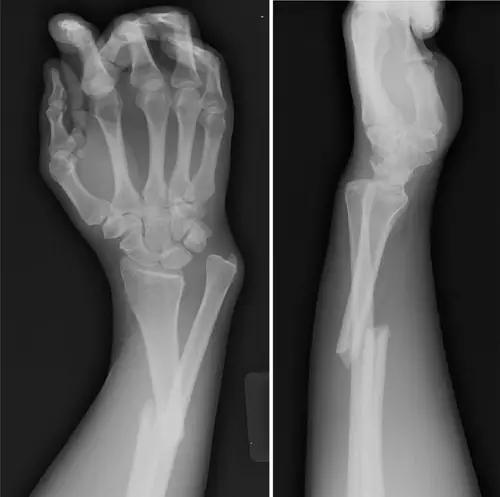

2. Colles 骨折

桡骨远端骨折,伴有桡骨远端向背侧的移位,可以有或没有尺骨干的骨折。具有这几个特征:背侧粉碎、向背侧成角、向背侧移位且挠骨短缩的关节外骨折。

典型 colles 骨折,枪刺样、餐叉样畸形

3. Smith 骨折

桡骨远端骨折伴骨折远端向掌侧移位,也称为反 Colles 骨折。

来源:radiology assistant